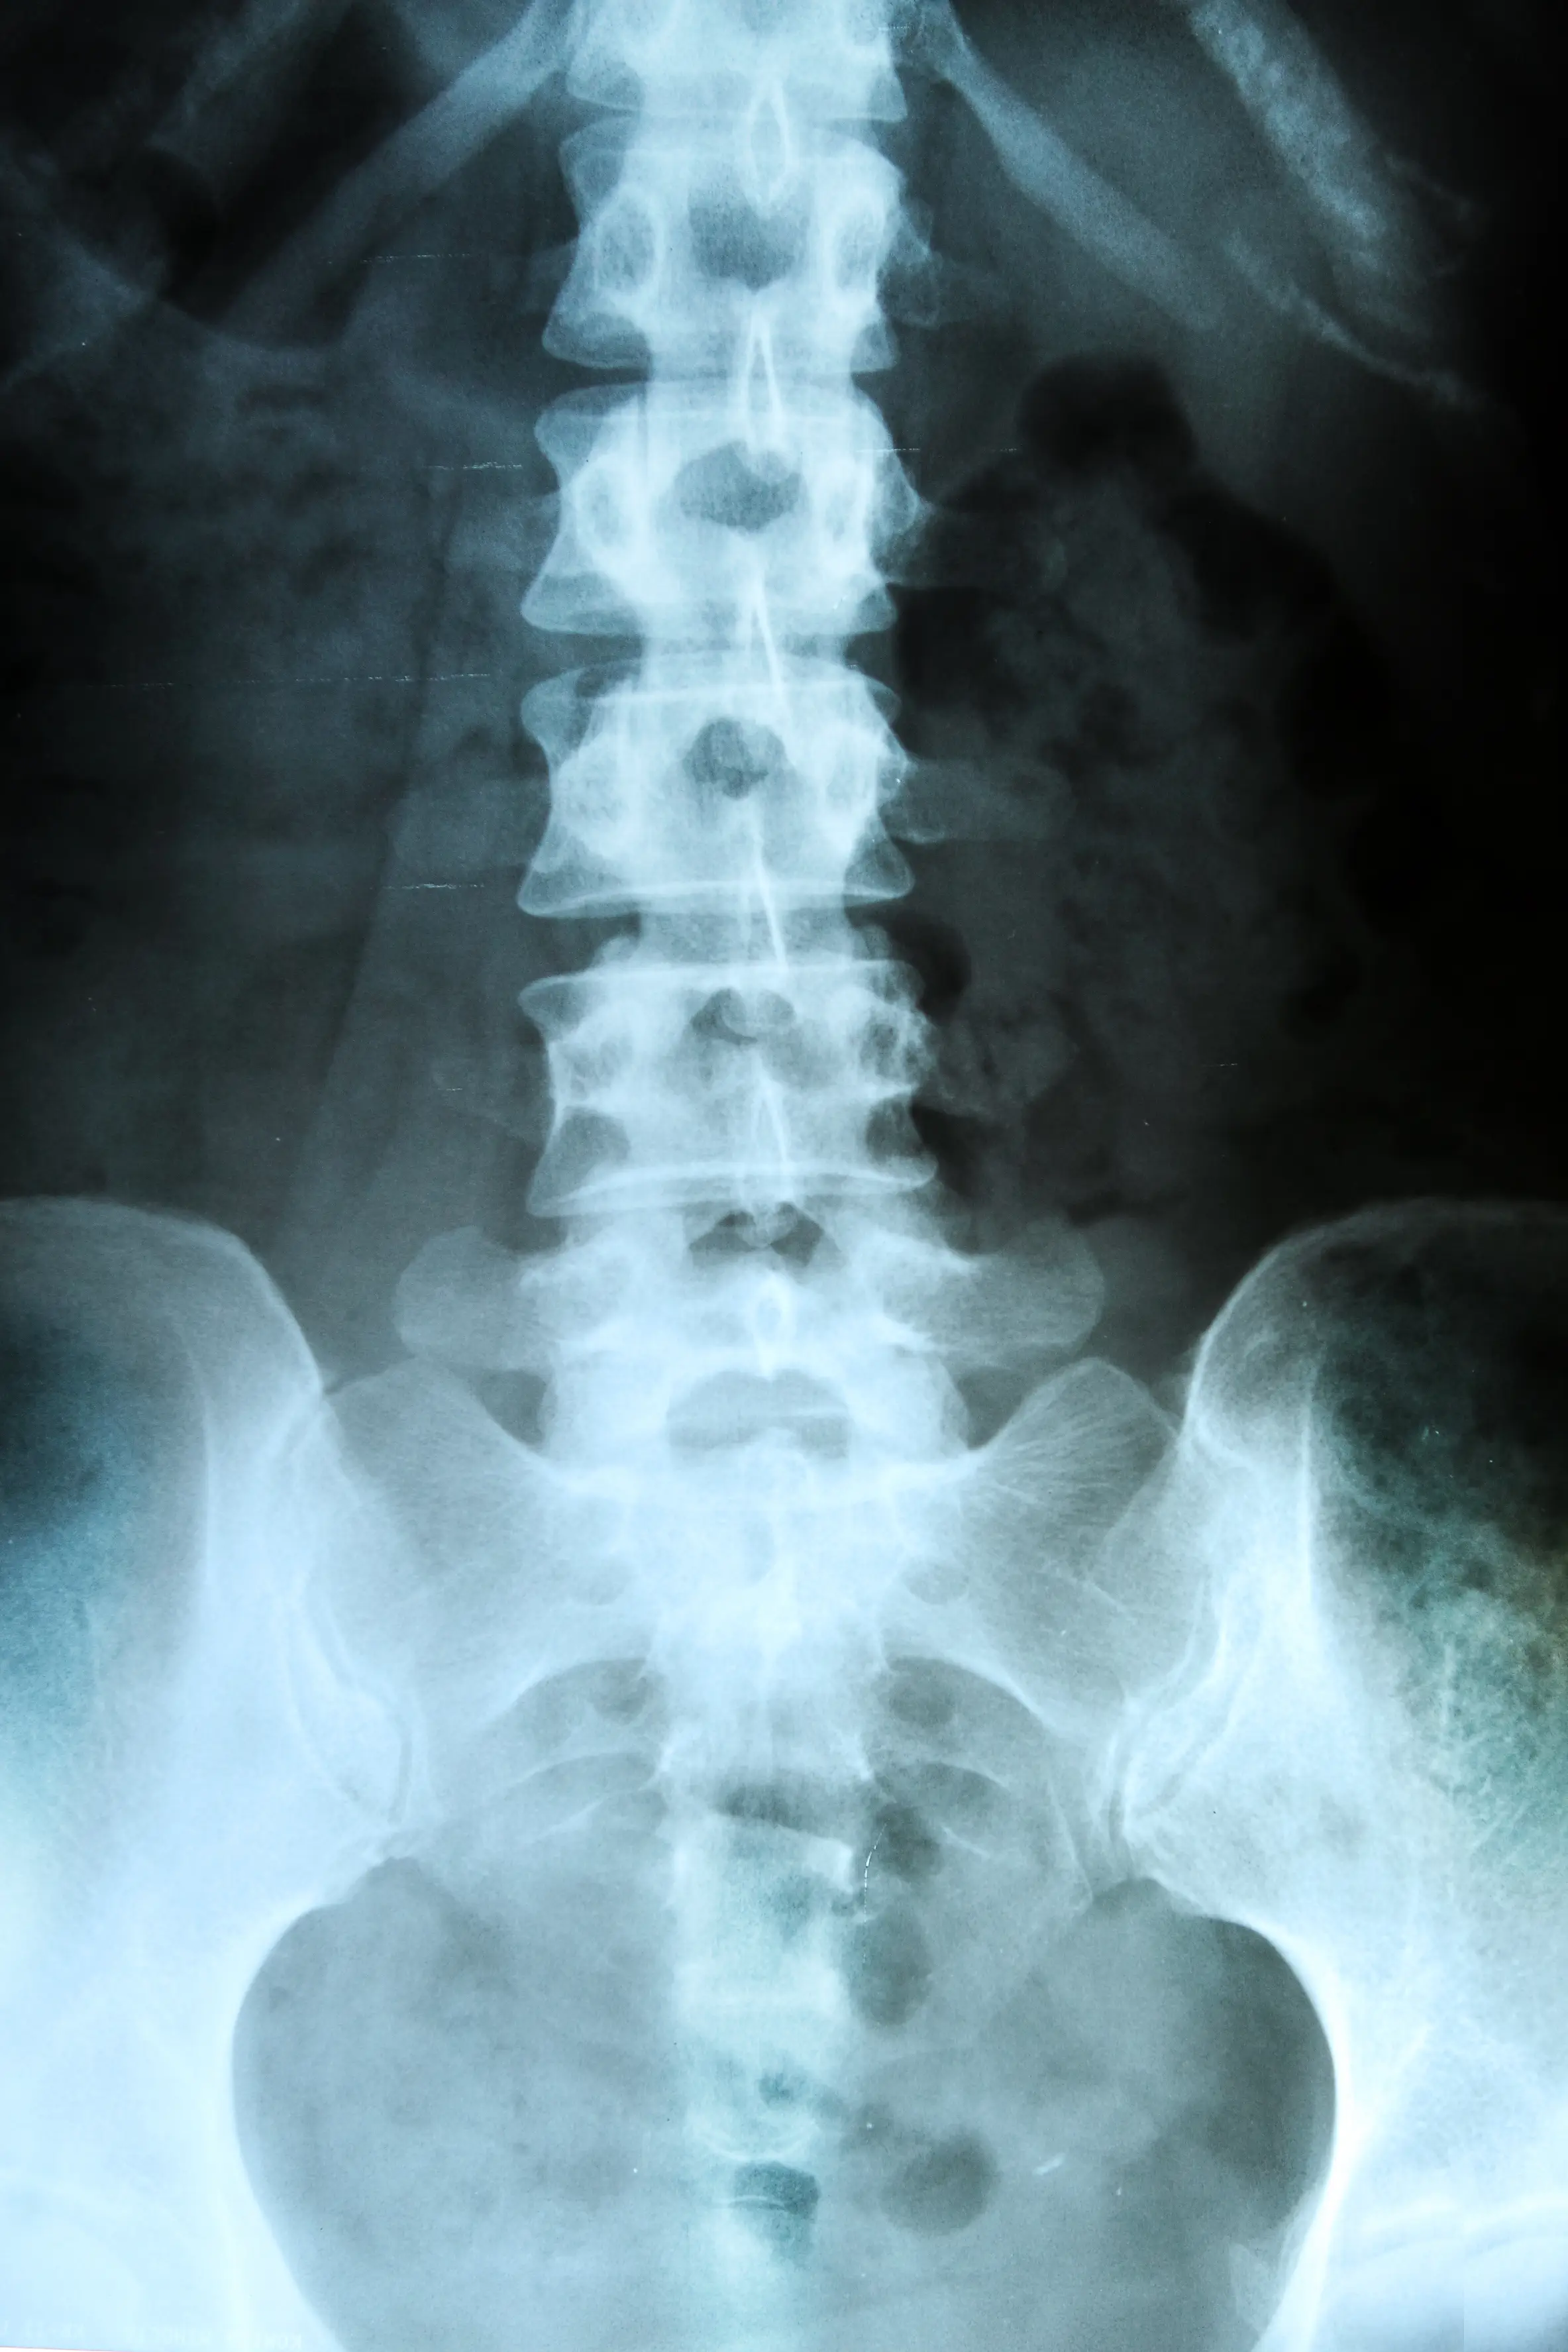

The health condition, which can affect both the brain and spinal cord, is also two to three times more common in women than it is in men, and some studies suggest that prevalence in women is increasing, according to the MS Trust.

In MS, the immune system attacks the layer that surrounds and protects the nerves called the myelin sheath.

"This damages and scars the sheath, and potentially the underlying nerves, meaning that messages travelling along the nerves become slowed or disrupted," the NHS notes.